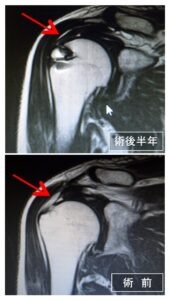

腱板を修復した場合は、1年を経過しても1年に1回MRIでの腱板の評価を勧めています

術後に再建腱板の評価をMRIで行います

菅谷分類

| Type1 | 腱板に厚み,一様に低信号 |

|---|---|

| Type2 | 腱板に厚み,一部に高信号混在 |

| Type3 | 連続性は保たれているが厚みがない |

| Type4 | 一部のスライスで連続性がない |

| Type5 | 連続性の途絶部分が大きい |

Type1(最もいい)~5(最も悪い)

4、5(再断裂)であっても求心位がとれていれば問題ありません。